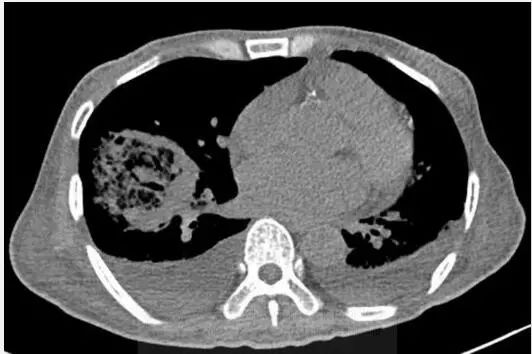

图1胸片示右肺下叶空洞性实变和左肺下叶实变。CT示右肺下叶类圆形实变伴中央磨玻璃影(反晕征),和空洞性病变。可见双侧胸腔积液。

支气管镜活检,真菌菌丝提示毛霉病。

诊断:毛霉病